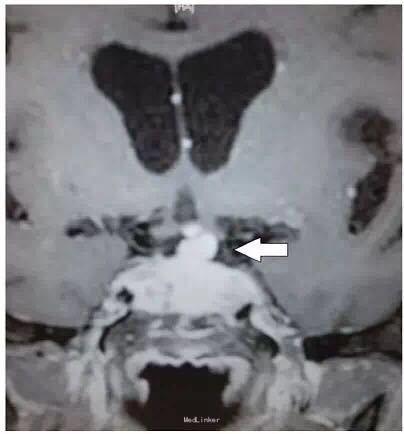

男性患者,82 岁,主因突发双眼复视和头痛就诊,既往有垂体大腺瘤病史。

体格检查显示双眼完全性上睑下垂。双侧动眼神经麻痹,右侧外展神经麻痹,水平性前庭 - 眼反射受损,瞳孔反射受损。视野和肌力检查正常。 血清钠为 112 mmol/L(正常值为 136-145 mmol/L);清晨皮质醇水平为 57 nmol/L(正常值为 171-536nmol/L)。甲状腺功能检查正常。

紧急行经蝶入路的垂体肿瘤全切术。在手术后动眼神经麻痹的症状有部分缓解。

表现为双侧动眼神经麻痹的垂体卒中十分罕见。垂体卒中是一种潜在威胁生命的疾病,以突发头痛、视力障碍、眼肌麻痹以及意识障碍为主要特征。垂体卒中是由垂体出血或梗死所致,大约 2/3 的患者伴有急性继发性肾上腺功能不足,这也是死亡的主要原因之一。